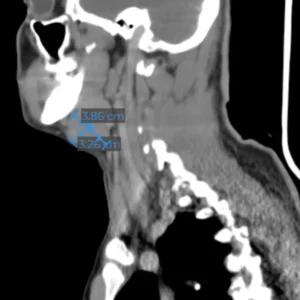

Hiperplasias o hipoplasias condilares

Es una enfermedad rara que se considera un crecimiento patológico y progresivo de uno o ambos cóndilos mandibulares, cuanto más grave es la patología, mayor asimetría y maloclusión desarrolla, que no solo afecta al desarrollo, masticación, deglución, habla, etc. si no que además esta particular entidad afecta altamente al individuo en un nivel psicosocial.